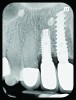

Fig 5. Radiograph 6 years after peri-implantitis repair (2014).

Figure 5